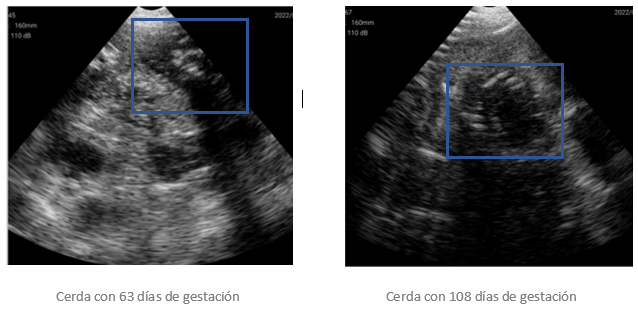

A continuación, adjuntamos algunas imágenes tomadas en granja:

En este tipo de equipos es posible ver preñeces muy claras a partir del día 23.